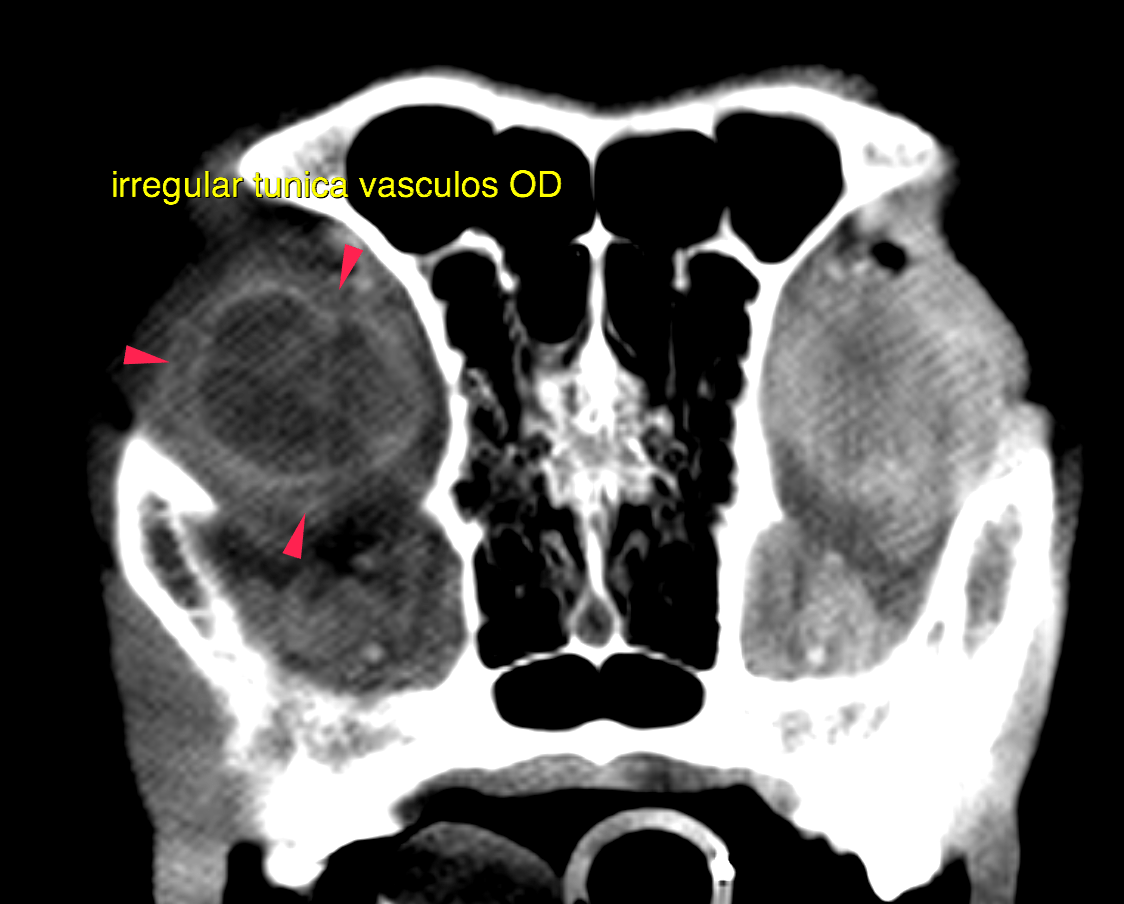

This 6 year old MN German Shepherd dog was diagnosed with hyphema, glaucoma and ocular trauma OD 3 week prior. Presented 2 days ago for ataxia and disorientation; CP deficits noted pelvic limbs. Chem: pre-renal azotemia.